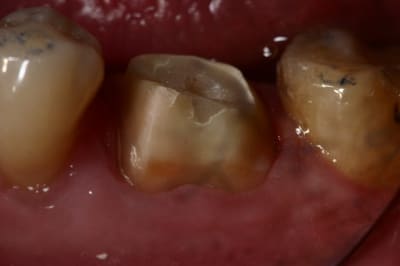

pour enfoncer le clou sur les tenons et autre inlay core

ne pas perdre de vue qu'un tenon = Rétention ... c'est tout !

Si on a de la rétention autrement, pas besoin de tenon...

Un tenon fragilise la racine et réduit l'étanchéité du traitement endo...

un cas comme on peut en faire souvent, d'endo couronne collée, exploitant le volume de la chambre pulpaire...

Et j'ajouterais que sur les photos que tu nous montres, tu as as réalisé un trottoir périphérique, pour réaliser qqchose qui ne correspond pas à la définition traditionnelle d'une endocouronne (qui est en réalité un onlay, avec prise de rétention interne).

C'est pas mal comme restauration, toutefois, tu as eu un peu de chance car l'endocouronne ne se prépare pas comme cela.

Tu a fais un mix entre la coiffe périphérique et l'endocouronne et il y a des risques de casse accrus. C'est dommage pour ces restaurations qui sont totalement inaltérables. Ce type de confusion dans les formes de préparations est très fréquent au début, et même un peu plus tard dans l'exercice. Il est certain que l'on a beaucoup de mal a lâcher les angrammes des restaurations classiques

Une endocouronne utilise le plancher caméral et sa forme de selle qui ne doit pas être fraisé et les parois sont ouvertes avec un maximum de 7° de TOC inversée.

La périphérie aplanie est si possible parallèle au plan occlusal ou perpendiculaire au sens d'application des forces.